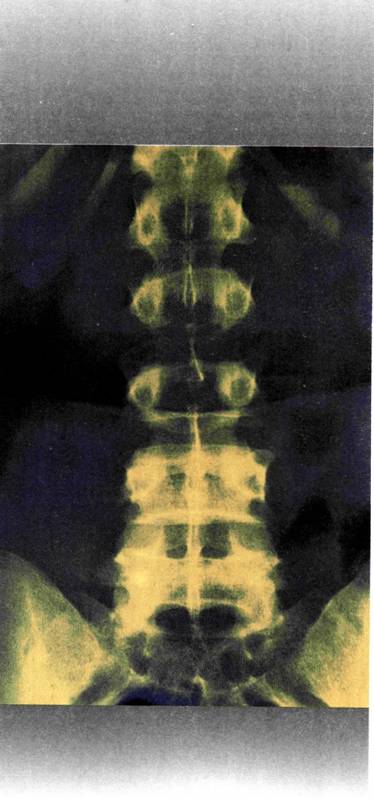

- Να βρείτε ακτινογραφίες διάφορων τμημάτων του σκελετού υγιών ατόμων, και αντίστοιχων τμημάτων

του σκελετού, ατόμων με παθήσεις των οστών. Να παρατηρήσετε και να καταγράψετε τις μεταξύ

τους διαφορές.